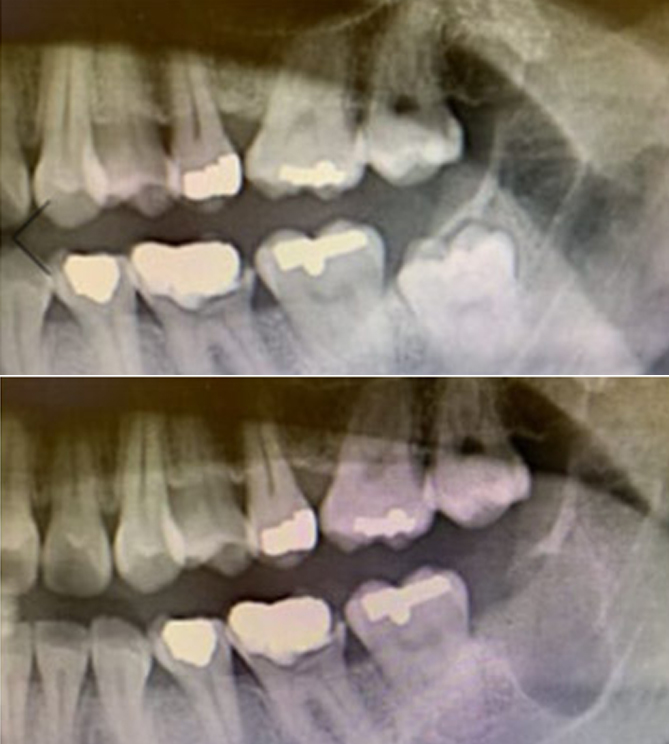

전후사진